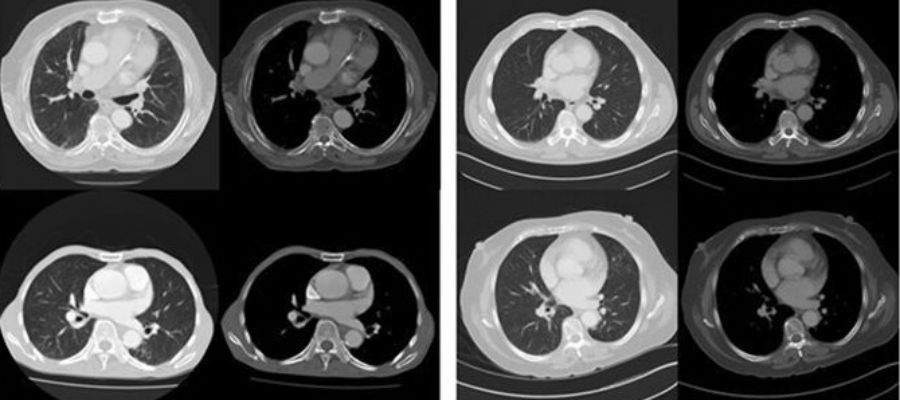

Dit computersysteem kan met bijna 70 procent zekerheid voorspellen of een patiënt komt te overlijden of niet.

Door naar CT-scans te kijken van 48 patiënten wist een robot met 69 procent nauwkeurigheid te voorspellen of ze zouden sterven binnen vijf jaar. En volgens de auteurs van het artikel komt dat percentage overeen met de voorspelling van menselijke artsen.

Om tot dit resultaat te komen, keek het systeem naar aandoeningen als een longemfyseem, een vergroot hart en vasculaire afwijkingen, zoals bloedstollingen. Het deep learning-systeem was getraind om meer dan 16.000 foto’s van menselijke rompen te analyseren om tekenen van ziekte in die organen te herkennen.

Terwijl de onderzoekers niet precies weten wat het computersysteem in de beelden zag om zijn voorspellingen te maken, werden de meest zelfverzekerde prognoses gemaakt bij patiënten met ernstige chronische ziekten, zoals emfyseem en veel voorkomende hartfalen.

Beeld: Oakden-Rayner et al